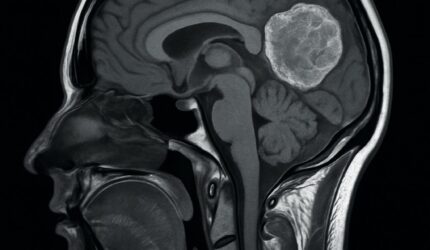

Tumores Cerebrais Têm Cura? O Que a Ciência Já Conquistou e o Que Vem Por Aí

Tumores cerebrais têm cura? Entenda os avanços da medicina no tratamento de gliomas, meningiomas e outros tipos de câncer no cérebro, e saiba o que esperar do futuro.Ler mais

Como é o Tratamento de um Tumor Cerebral? Entenda as Etapas e Opções Disponíveis

Saiba como funciona o tratamento de tumores cerebrais, incluindo cirurgia, radioterapia e novas terapias. Entenda as opções de cuidado e os avanços recentes.Ler mais

Tipos de Tumores Cerebrais Mais Comuns Explicados de Forma Simples

Conheça os principais tipos de tumores cerebrais, como gliomas, meningiomas e meduloblastomas, explicados de forma acessível para pacientes e familiares.Ler mais

Tumores Cerebrais: Quais os Primeiros Sintomas Que Você Não Deve Ignorar

Descubra os principais sinais de alerta dos tumores cerebrais, como dor de cabeça persistente, convulsões e alterações de comportamento. Diagnóstico precoce pode salvar vidas.Ler mais